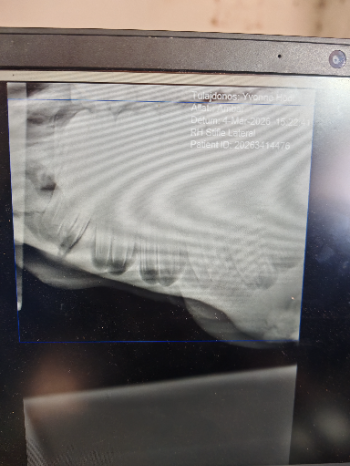

Ambar, unser junger Hengst, steht in der Tierklinik und hat gerade seine zweite große Operation am Unterkiefer hinter sich. Eine Zyste unter der Zahnwurzel hat den Kieferknochen zerstört, die Nekrotisierung ist weit vortgeschritten – jetzt wird er mehrfach operiert und muss monatelang heilen. Wenn alles gut verläuft, kann er in rund acht Monaten wieder vollständig gesund sein.

Bisherige Kosten 3800 Euro